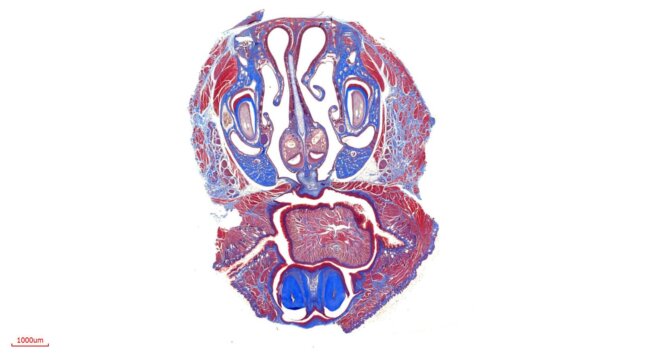

特殊染色

By

立众小編1號

2021-07-01